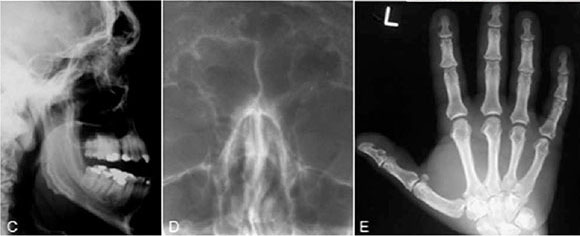

Below are clinical and radiographic images of a condition in which the terminal phalanges of the hands and the feet are enlarged. Growth of the mandibular condyle results in marked prognathism, and this together with macroglossia, leads to dental malocclusion. Which radiograph points most directly to the diagnosis?

All the features mentioned above as well as the enlarged pituitary fossa/sella tursica (Figure C) is suggestive of acromeg aly. Hyperpituitarism is generally idiopathic in children and is caused by an acidophilic adenoma of the anterior lobe of the pituitary gland in adults. In childhood, hyperpituitarism leads to gigantism; in adulthood it causes acromegaly. Both are caused by an increased secretion of growth hormone stemming from an eosinophylic hyperplasia or in most cases as eosinophylic adenoma of the anterior pituitary gland. The disorder is most frequently seen between the ages of 20 and 40 years, but onset of the condition is often in late adolescence. Males and females are equally affected. When hyperpituitarism occurs after epiphyseal closure, acromegaly results. The terminal phalanges of the hands (Figure E) and of the feet are enlarged, and the ribs are increased in size. Growth of the mandibular condyles and rami results in marked prognathism, and this together with macroglossia (Figure B) leads to dental malocclusion. Spreading of the teeth, especially of the mandibular incisors, is a most characteristic change and is often an early symptom. The enlarged tongue shows indentations on the sides because of pressure against the teeth. The skin is coarse, and the lips become thickened. Headaches, photophobia, and reduced vision may also be present. Radiographically, one sees most frequently an enlarged sella tursica (Figure C) and a dramatic increase in size of the frontal sinuses (Figure D). Apart from the relatively frequent mandibular protrusion, a flattening of the gonial angle (Figure A) is often seen in acromegaly. Resorption of the roots as well as excessive hypercementosis has been reported. Therapeutically, the adenoma of the pituitary gland is treated surgically or by radiotherapy.